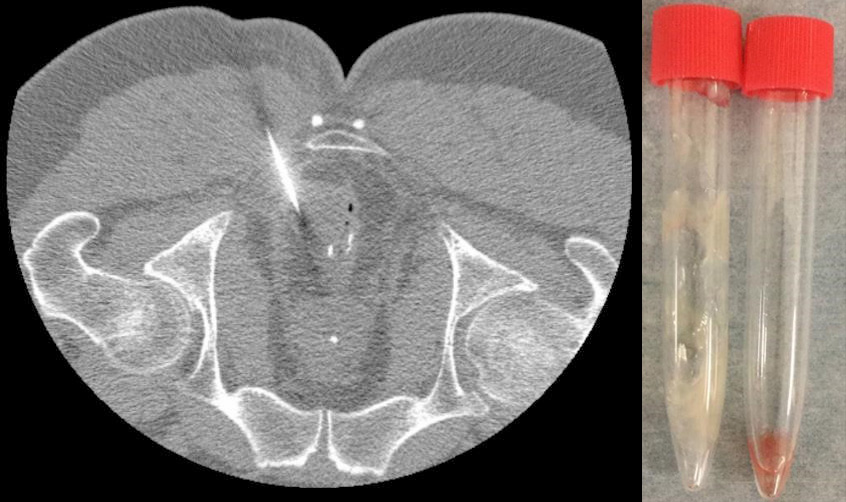

• 直腸粘膜下に造影効果を伴わない低濃度腫瘤。

• 腫瘤の周囲には吻合に使用されたステイプルを認める。

直腸癌の手術から7年経過しており、腫瘍マーカーの上昇もないことから、吻合部再発よりもimplantation cystが疑われた。悪性腫瘍の除外目的でCTガイド下穿刺が行われ、粘液が採取され、細胞診は陰性であった。3か月後のCTで増大を認めたが、その後のフォローでは増大はみられなかった。

CT、MRIでは吻合部近傍の嚢胞性病変として認められる。文献および自験例からはステイプルリングを嚢胞が圧排する像が特徴的と思われる。内視鏡では吻合部の粘膜下腫瘤の像を呈し、EUSでは第3層または第4層と連続する嚢胞として描出される。FDG-PETでは基本的に集積を認めない。臨床上は粘液癌の再発との鑑別が問題となる。